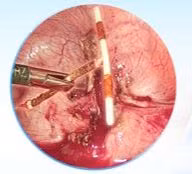

(khoahocdoisong.vn) - Nhờ phẫu thuật cấp cứu khẩn cấp các bác sĩ bệnh viện Nội Tiết T.Ư đã cứu sống được bệnh nhân bị u bàng quang gây bí tiểu, bàng quang nhiều máu cục, sốc mất máu kèm đường huyết tăng cao...